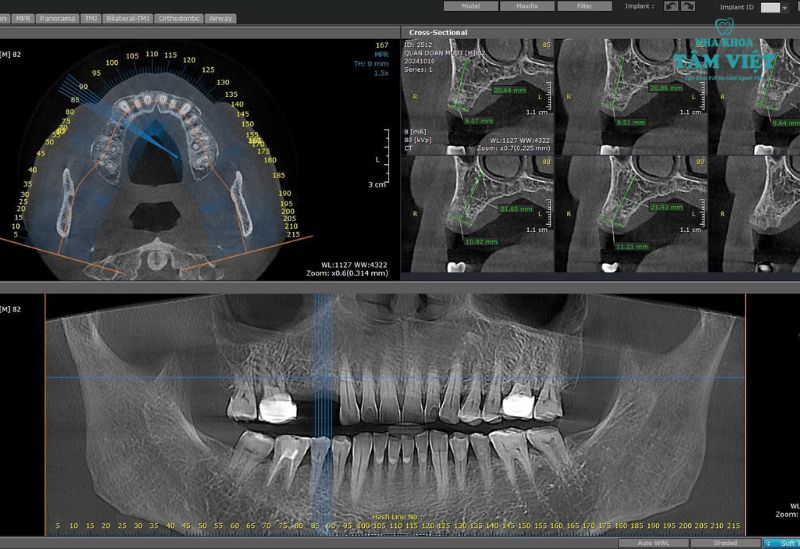

- Thực hiện chụp phim X-quang và CT Scan: Để đảm bảo quá trình cấy ghép implant được thực hiện chính xác, nha sĩ sẽ thực hiện chụp phim X-quang và CT Scan để đánh giá được chính xác tình trạng xương hàm và lên phác đồ điều trị cụ thể.